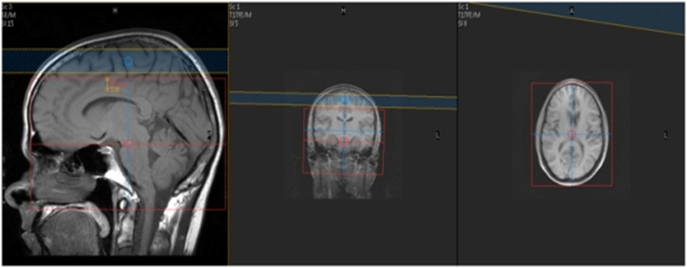

| SAG | T1 | TSE | 4mm | 1mm | None | S | Scalp to Scalp |

| AXIAL | T2 | TSE | 4mm | 1mm | None | 23cm | Angle to Corpus- Skull Base to Vertex |

| AXIAL | T1 | TSE | 4mm | 1mm | None | 23cm | Angle to Corpus- Skull Base to Vertex |

| AXIAL | T2* GRE | GRE | 4mm | 1mm | None | 23cm | Angle to Corpus- Skull Base to Vertex |

| AXIAL | DWI 2mm Voxel | SE EPI | 3mm | 0.3mm | SPIR | 23cm | Angle to Corpus- Skull Base to Vertex |

| AXIAL | FLAIR | TSE | 4mm | 1mm | None | 23cm | Angle to Corpus- Skull Base to Vertex |